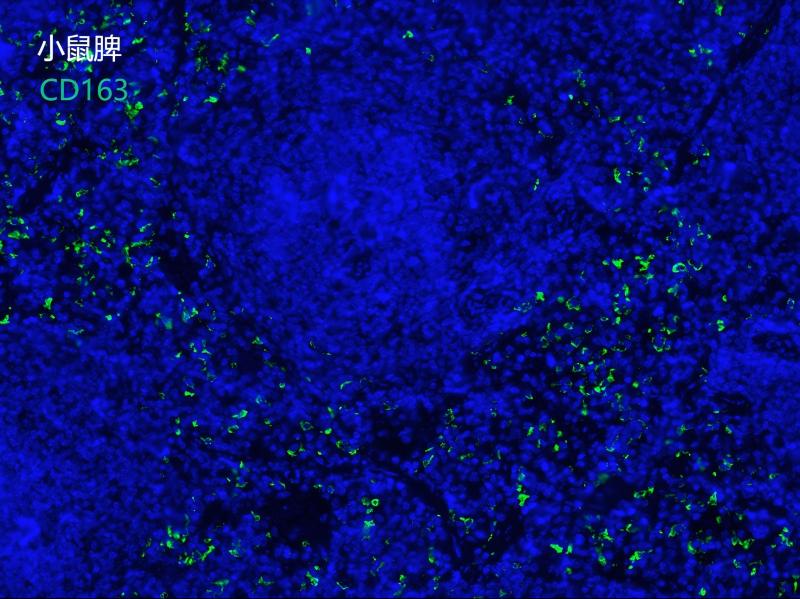

CD163

• 反应种属:Human Mouse Rat

应用 IHC-P, mIHC,WB,IF

使用方法 WB 1:100-1:1000IHC-P 1:250-1:1000mIHC 1:250-1:1000IF 1:500IP 1:25

CD163 is a monocyte/macrophage specific marker expressed predominantly on cells which possess strong anti-inflammatory potential. The expression of CD163 is strongly induced by anti-inflammatory mediators such as glucocorticoids and interleukin-10, while being inhibited by pro-inflammatory mediators such as interferon-gamma. CD163-expressing mononuclear phagocytes, as well as soluble CD163, may both take part in downregulating an inflammatory response.